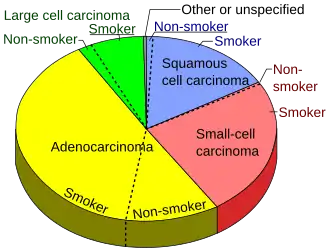

The most common types of NSCLC are squamous-cell carcinoma, large-cell carcinoma, and adenocarcinoma, but several other types occur less frequently. A few of the less common types are pleomorphic, carcinoid tumor, salivary gland carcinoma, and unclassified carcinoma.[5] All types can occur in unusual histologic variants and as mixed cell-type combinations.[6] Non-squamous-cell carcinoma almost occupies the half of NSCLC. In the tissue classification, the central type contains about one-ninth.

Lung cancer in people who have never smoked is almost universally NSCLC, with a sizeable majority being adenocarcinoma.[7]

Adenocarcinoma of the lung is currently the most common type of lung cancer in "never smokers" (lifelong nonsmokers).[10] Adenocarcinomas account for about 40% of lung cancers. Historically, adenocarcinoma was more often seen peripherally in the lungs than SCLC and squamous-cell lung cancer, both of which tended to be more often centrally located.[11][12] Recent studies, though, suggest that the "ratio of centrally to peripherally occurring" lesions may be converging toward unity for both adenocarcinoma and squamous-cell carcinoma.

Squamous-cell carcinoma (SCC) of the lung is more common in men than in women. It is closely correlated with a history of tobacco smoking, more so than most other types of lung cancer. According to the Nurses' Health Study, the relative risk of SCC is around 5.5, both among those with a previous duration of smoking of 1 to 20 years and those with 20 to 30 years, compared to "never smokers" (lifelong nonsmokers).[13] The relative risk increases to about 16 with a previous smoking duration of 30 to 40 years and roughly 22 with more than 40 years.[13]

Large-cell lung carcinoma (LCLC) is a heterogeneous group of undifferentiated malignant neoplasms originating from transformed epithelial cells in the lung. LCLCs have typically comprised around 10% of all NSCLCs in the past, although newer diagnostic techniques seem to be reducing the incidence of diagnosis of "classic" LCLC in favor of more poorly differentiated SCCs and adenocarcinomas.[14] LCLC is, in effect, a "diagnosis of exclusion", in that the tumor cells lack light microscopic characteristics that would classify the neoplasm as a small-cell carcinoma, squamous-cell carcinoma, adenocarcinoma, or another more specific histologic type of lung cancer. LCLC is differentiated from SCLC primarily by the larger size of the anaplastic cells, a higher cytoplasmic-to-nuclear size ratio, and a lack of "salt-and-pepper" chromatin.

- ^ Smokers defined as current or former smokers of more than 1 year of duration. See image page in Commons for percentages in numbers. Reference: Table 2 in: Kenfield SA, Wei EK, Stampfer MJ, Rosner BA, Colditz GA (June 2008). "Comparison of aspects of smoking among the four histological types of lung cancer". Tobacco Control. 17 (3): 198–204. doi:10.1136/tc.2007.022582. PMC 3044470. PMID 18390646.